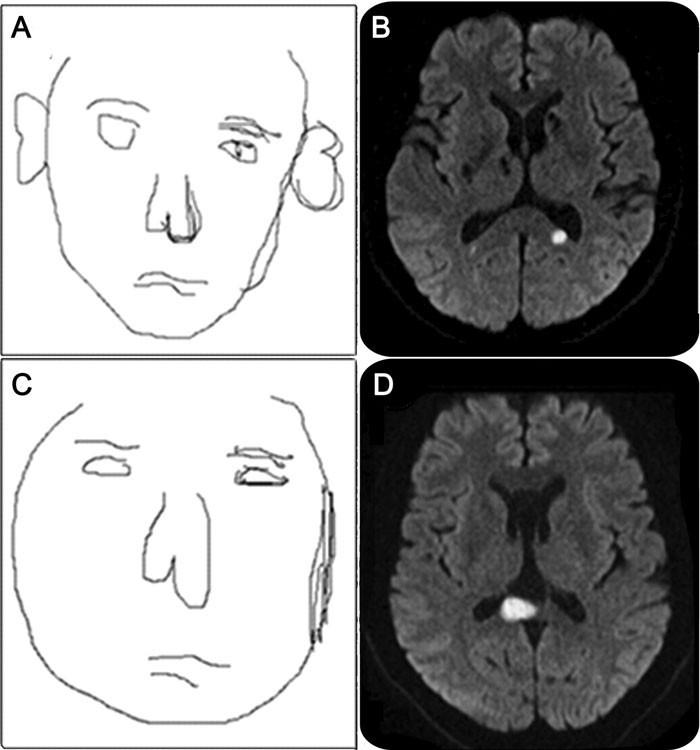

In the 2011 case, published by The Lancet three years later, the woman reported that faces “turned black, grew long pointy ears and a protruding snout, and displayed a reptiloid skin and huge eyes in bright yellow, green, blue, or red.”

According to the report, the results were normal. However, an MRI of her brain showed several lesions near the lentiform nucleus. Damage to this part of the brain has been linked to cognitive impairments, such as issues with memory and processing speed, and is associated with schizophrenia and other neurological and psychiatric disorders.

The doctors suspect that the lesions revealed by the MRI may have triggered atypical electrical activity in the ventral occipitotemporal cortex, the part of the brain that processes colors and faces.

Image credits: Mello, Antônio et al. The Lancet, Volume 403, Issue 10432, 1176

Considering the findings, they diagnosed the patient with a form of prosopometamorphopsia (PMO), an extremely rare neurological disorder that causes faces to appear distorted in shape, texture, position, or color.

Doctors theorized that lesions in her brain caused atypical electrical activity in the brain region responsible for processing faces